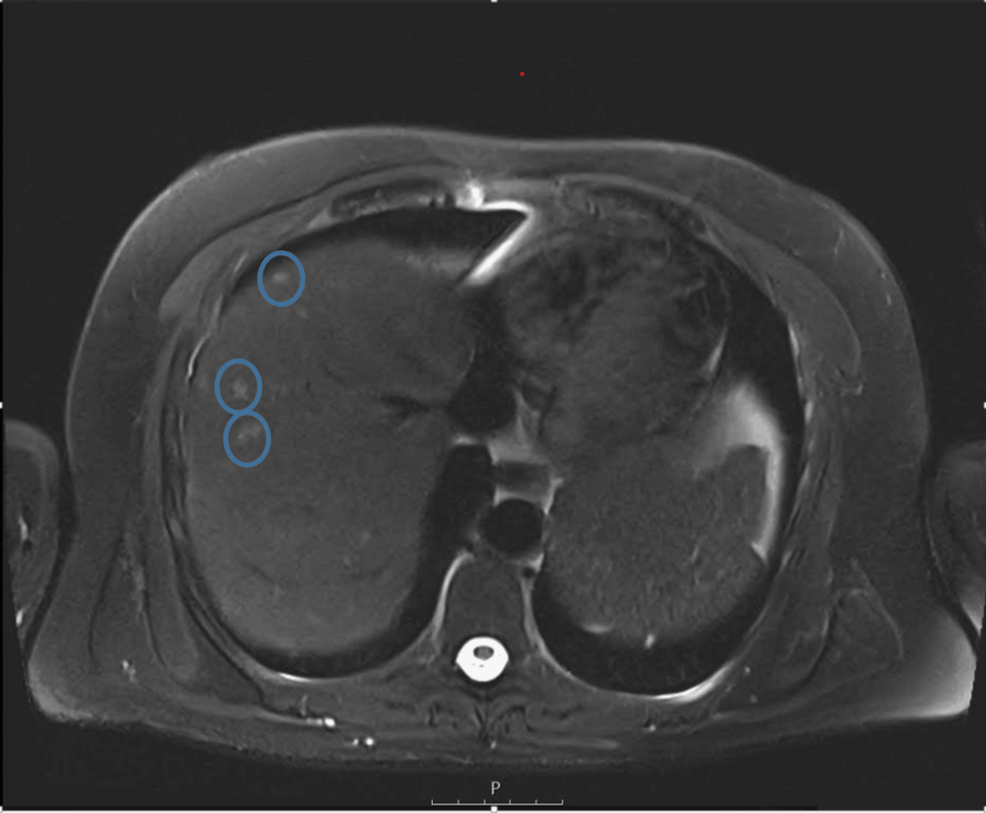

The patient arrived with systemic symptoms and imaging that revealed multifocal lesions in the liver and spleen. Early interpretations leaned toward malignancy, a possibility that carried notable implications for treatment planning and prognosis.

- CT scan: Multiple hypodense lesions with peripheral enhancement; “target” appearance may suggest both TB granulomas and metastatic disease.

- MRI: T2‑hyperintense lesions with central necrosis; diffusion‑weighted imaging (DWI) shows restricted diffusion in both entities, necessitating further work‑up.

- Imaging: Contrast‑enhanced CT revealed multiple low‑attenuation lesions in liver and spleen, raising suspicion for metastatic carcinoma.

Role of Imaging Modalities in Distinguishing TB from Metastasis

| MRI with hepatocyte‑specific contrast | Superior soft‑tissue contrast; detects small lesions | Costly, limited access in low‑resource settings |